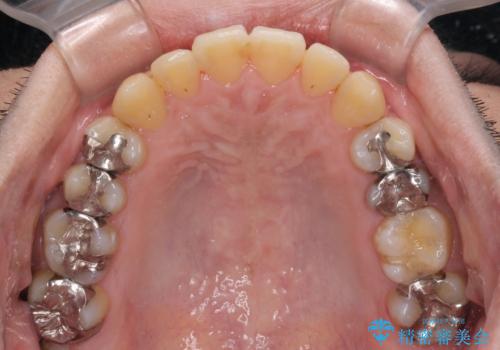

前歯のクロスバイトをインビザラインで矯正治療

- 前歯のデコボコとクロスバイトを気にして来院された患者様です。

前歯を早く整えたいとの希望があったので、ワイヤー矯正にて短期間でクロスバイトを解消し、その後インビザラインにて整えることとしました。

インビザラインによる前歯のクロスバイト改善におけるリスクとして、前歯歯髄充血・歯髄壊死が挙げられます。

ワイヤー矯正を併用する目的として、短期間でデコボコやクロスバイトを改善する他に、歯髄充血リスクを低減させるというものがあります。